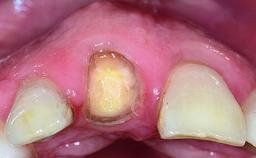

A healthy 28-year-old female patient presented for a consultation on treatment options to restore her upper right central incisor. At the clinical examination, the tooth responded to percussion and palpation. The gingiva was red and slightly swollen, with a mid-facial probing depth of 10 mm. The upper right lateral incisor showed no signs or symptoms, did not respond to exploration and percussion, and the vitality test was positive. The periapical radiograph revealed that tooth 11 had been endodontically treated, with no lesion evident at the apex. A small radiopaque calcified structure surrounded by a narrow radiolucent zone (3 × 3 mm) was present at the apex of tooth 12.

Provisional Implant-Supported Prosthesis Prosthodontic margin > 3 mm apical to mucosal margin Prosthodontic margin > 3 mm apical to mucosal margin